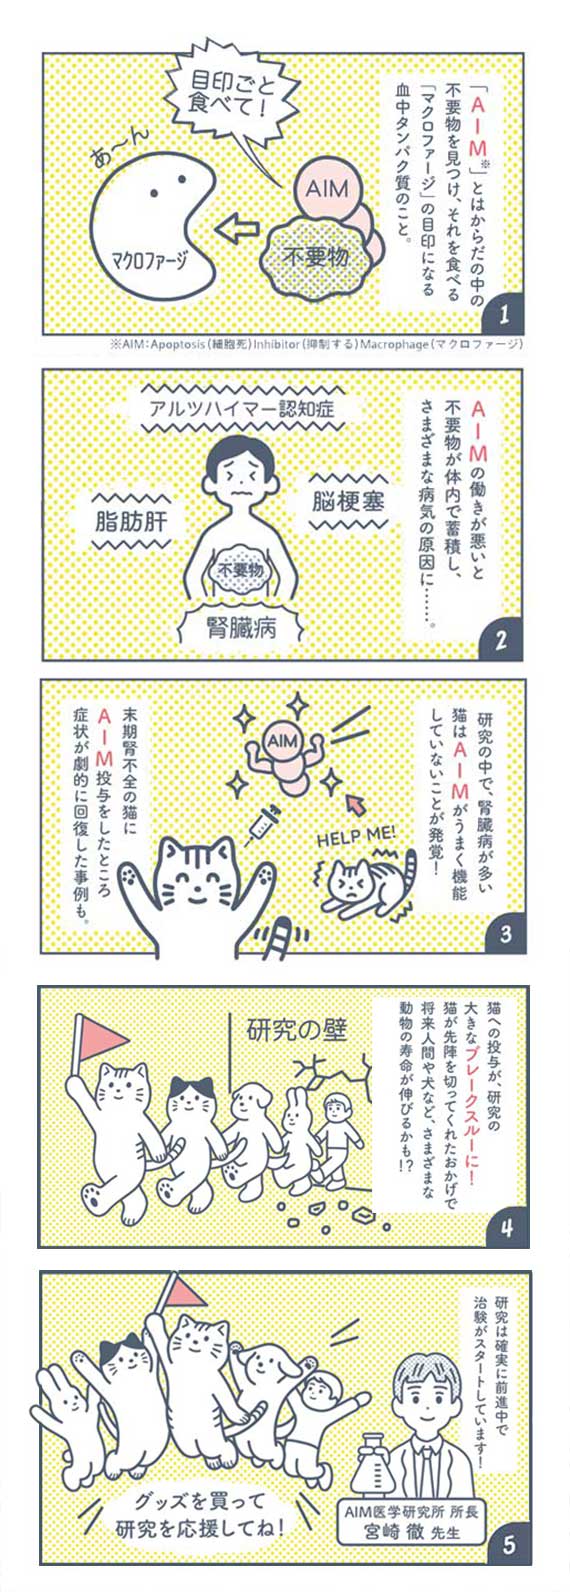

腎臓病診療の最先端No.30, サポーターになって応援しよう!猫の,

サポーターになって応援しよう!猫の, Impella RP Flex with SmartAssistが右心不全の治療としてFDA,

Impella RP Flex with SmartAssistが右心不全の治療としてFDA, 猫の腎臓病治療薬開発につながる「AIM医学研究」を支援する,

猫の腎臓病治療薬開発につながる「AIM医学研究」を支援する, Impella RP Flex with SmartAssistが右心不全の治療としてFDA,